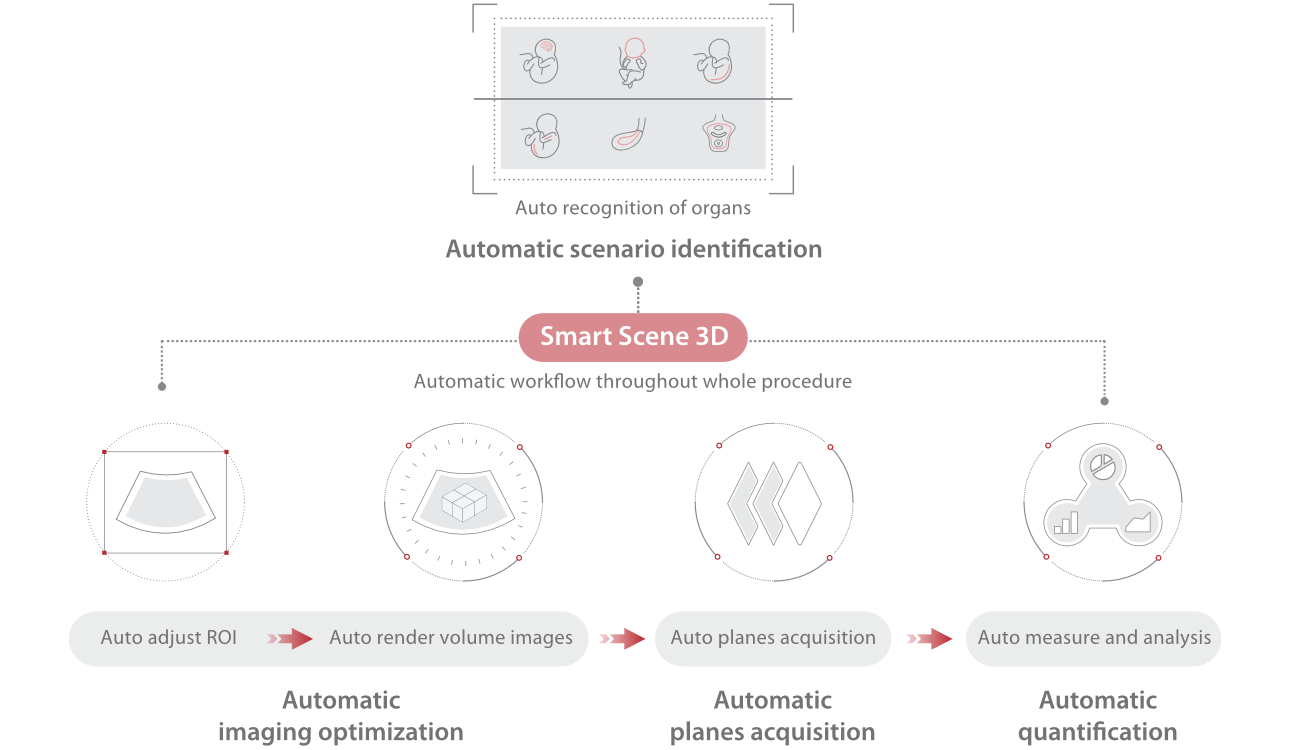

Full-stack Solution Powered by ZST?+

The ZST+ platform is an extraordinary innovation, representing an ultrasound evolution. Transforming ultrasound metrics from conventional beam-forming to channel data based processing. It overcomes the traditional trade-off limitation among spatial resolution, temporal resolution and tissue uniformity, delivering exceptional image quality for infinite imaging solutions with non-stop improvements.